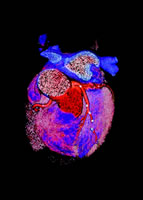

冠状动脉钙化(CAC)是动脉粥样硬化的一部分。在粥样硬化动脉中均存在钙化,而在正常动脉管壁则很少见。因而,及时检测CAC可早期发现冠脉粥样硬化。最近美国心脏病学会基金会(ACCF)和美国心脏学会(AHA)发布了专家共识,介绍了通过CT检测CAC积分在评估整体心血管危险和评价胸痛患者中的应用。